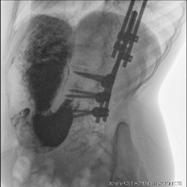

A Urgències es canalitza via venosa i s'extreu analítica sanguínia que no mostra alteracions (hemograma, bioquímica, equilibri àcid-base i ionograma normals, no elevació de reactants de fase aguda). Es realitza radiografia de tòrax (normal). Valorada conjuntament amb l'equip de Gastroenterologia, es decideix ingrés hospitalari per ampliar estudi sota tractament amb protector gàstric (omeprazol endovenós) i dieta absoluta amb sueroteràpia a necessitats basals. Durant el primer dia d'ingrés, es realitza un trànsit esòfag-gastroduodenal, on s'observa contingut heterogeni a l'interior de l'estómac, suggestiu de material alimentari, així com defecte de repleció a la part central de la llum al pílor o porció duodenal, sense aconseguir una progressió del contrast més enllà d'aquesta regió.

Figura

esòfag-gastroduodenal. S'observa defecte de repleció a la part central de la llum del pílor o porció duodenal.

1. Trànsit